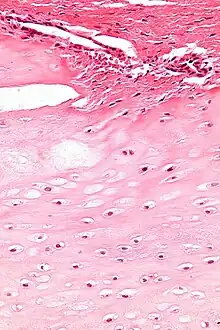

Micrograph of an enchondroma. H&E stain.

Enchondroma is a type of benign bone tumor that originates from cartilage. The exact etiology of it is not known. An enchondroma most often affects the cartilage that lines the inside of the bones. The bones most often involved with this benign tumor are the miniature long bones of the hands and feet. It may, however, also involve other bones such as the femur, humerus, or tibia. While it may affect an individual at any age, it is most common in adulthood. The occurrence between males and females is equal. It is not very likely that the enchondroma will grow back in the same spot; the rate is less than ten percent.